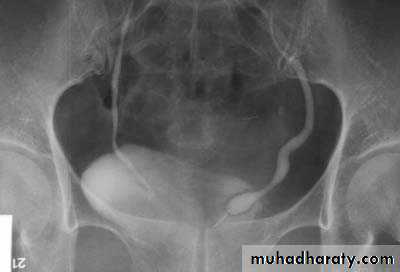

bladder exstrophy

radiographic appearance in bladder exstrophy. It describes wide midline separation of the pubic bones.Bladder exstrophy (also known as ectopia vesicae) refers to a herniation of the urinary bladder through an anterior abdominal wall defect. The severity of these defects is widely variable.